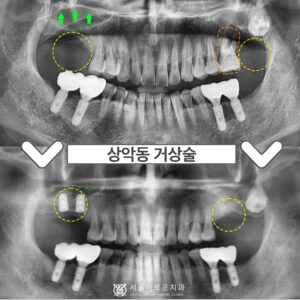

부천서울이로운치과 상악동 거상술을 동반해야 한다면

부천서울이로운치과 상악동 거상술을 동반해야 한다면 안녕하세요 😊 내 치아에 이로운 치과 서울이로운치과입니다 🙂 오늘은 임플란트 중에서도 난이도가 높은 “상악동 거상술” 케이스를 설명드리겠습니다. 왼쪽 위 어금니가 아파요.…